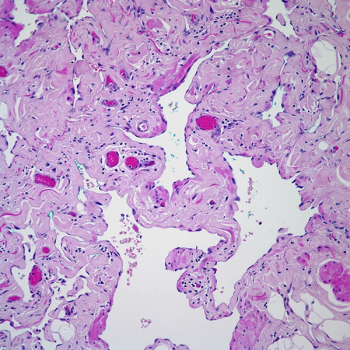

A 21-year-old woman develops a nodule in her left breast, and a biopsy is obtained. What your diagnosis?